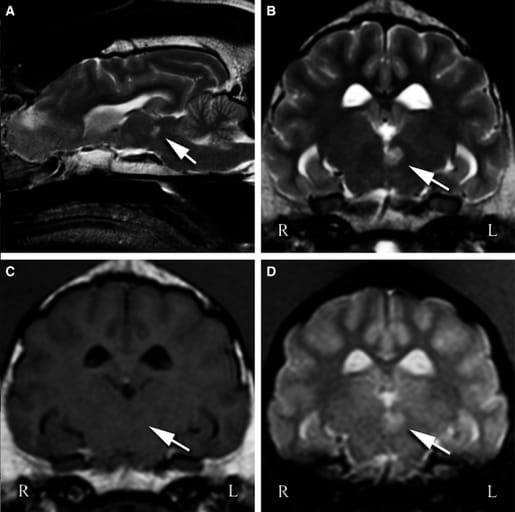

Case 3 T2-weighted sagittal image of the brain (A) and T2W (B), T1W (C), and FFE (D) transverse images at the level of the rostral midbrain revealed a round, well-demarcated lesion adjacent to the midline (left sided) and ventrolateral to the rostral part of the mesencephalic aqueduct. The lesion (indicated by the arrows) is hyperintense-to-normal-gray matter on T2W and FFE sequences, and is iso- to hypointense on T1W sequences.